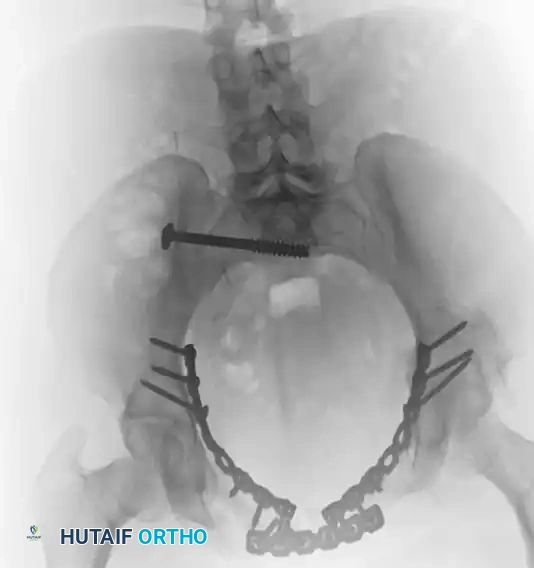

The following radiographic series demonstrates the successful transition to definitive internal fixation in a vertically unstable pelvic fracture, utilizing an anterior symphyseal plate and a posterior sacroiliac screw:

TREATMENT Surgical Diagram

Postoperative Anteroposterior (AP) view demonstrating definitive internal fixation. Note the reduction of the symphysis pubis with a multi-hole plate and the stabilization of the posterior ring with an iliosacral screw.